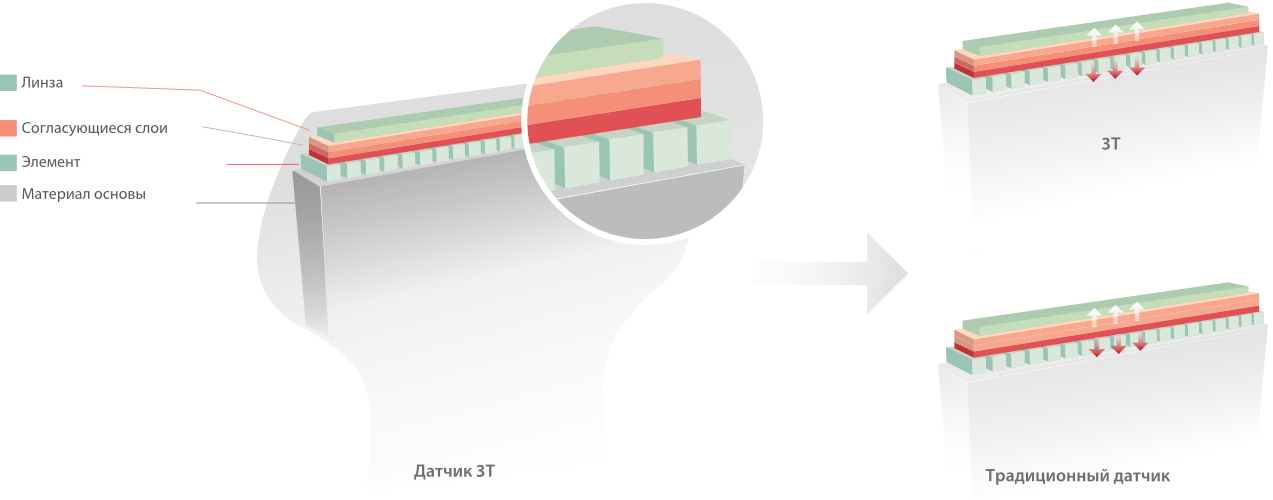

Портативная ультразвуковая система M8 от компании Mindray, основанная на зарекомендовавшей себя компактной платформе mQuadro, разработана для обеспечения более доступных возможностей премиум-класса и ориентирована на быструю и точную диагностику. M8 — это универсальная система с широким спектром применения.